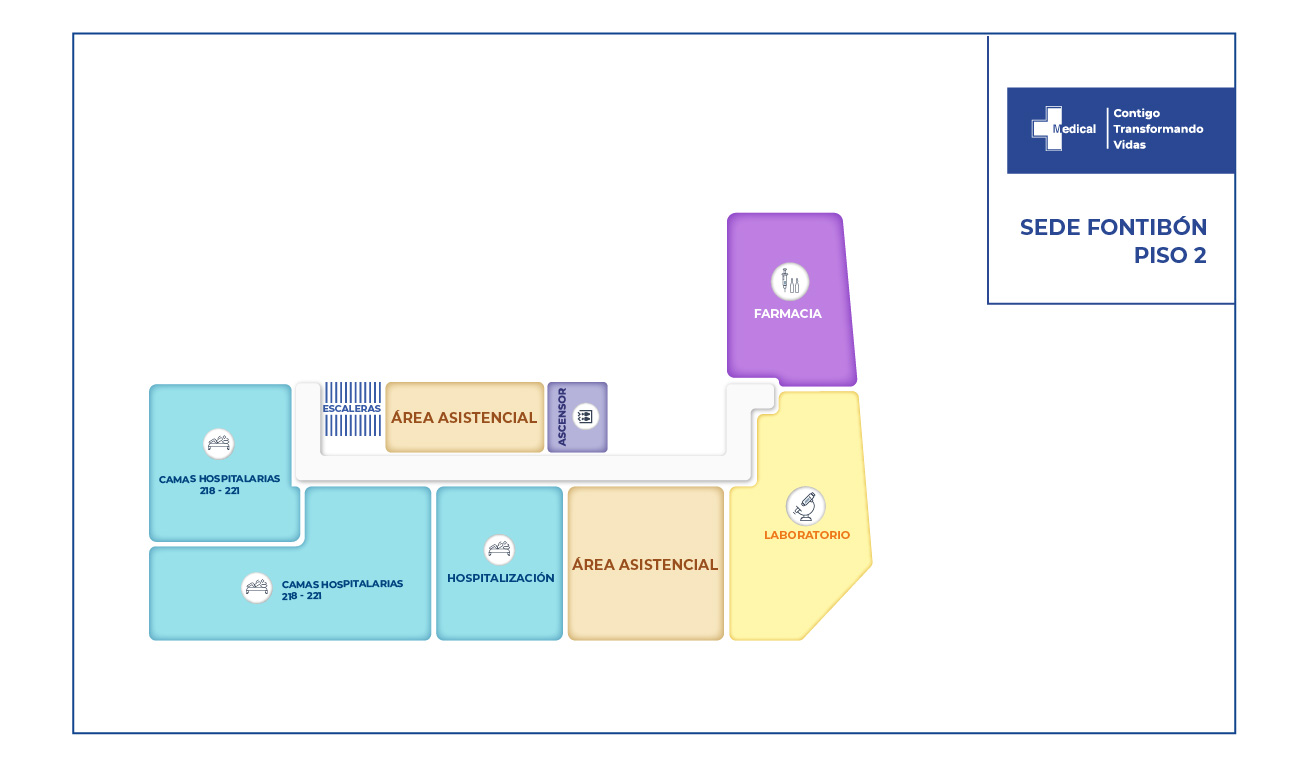

La condición de ingreso es realmente poco alentadora, sin embargo la oportunidad de los servicios, la eficiencia y eficacia que caracteriza a la clínica Medical SAS, ofrece al paciente y su familia todo un equipo interdisciplinario para la atención adecuada y secuencial para este tipo de traumas. Precedida por especialistas en cirugía general, neurocirugía, psicología, psiquiatría, servicios de apoyo terapéutico y radiológico, salas de cirugía, unidad de cuidados intensivos, rehabilitación física, clínica de heridas, entre otros.

El paciente fue sometido a 3 cirugías y 6 procedimientos realizados entre cirugía general como tratamiento a través de toracostomia, de igual manera descarto lesiones abdominales por trauma cerrado y neurocirugía realiza la reparación de la fistula espinal de líquido cefalorraquídeo, la reducción abierta de fractura de columna vertebral y artrodesis de la región torácica (consistió en la colocación de 20 tornillos transpediculares, 2 barras verticales y 1 conector transverso, esto en 10 segmentos).

Desde el ingreso fue claro que el paciente no recobraría la movilidad de las piernas dada a la sección medular completa, sin embargo el equipo de especialistas intervino al paciente con la finalidad de evitar deformidad mayor en la columna vertebral, disminuir el riesgo de fracturas a otro nivel vertebral, adopción de una postura más estable, disminución de dolor. Todas ellas enfocadas en brindar al joven paciente una opción de mejorar su calidad de vida.